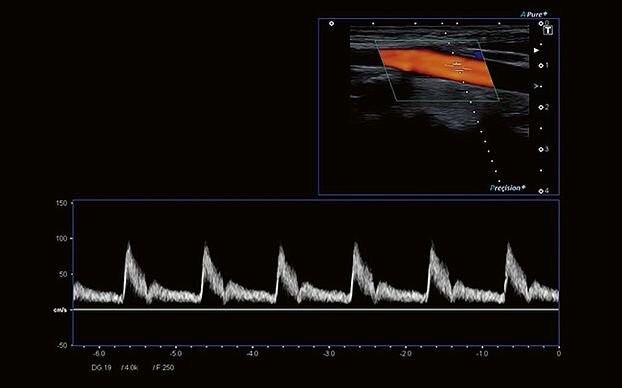

- Импульсно-волновой/постоянно-волновой доплер PWD/CWD

- Цветной доплер CFM

- Технология Precision Imaging

- Технология ApliPure+: многолучевое сканирование в реальном времени для повышения качества изображения

- Постоянно-волновой доплер - функция, где вы сможете проводить количественную оценку кровотока в сосудах с высокоскоростными потоками, что активно используется в исследованиях эхокардиографии

- Цветной доплер - эта функция поможет в исследованиях сердечно-сосудистой системы. Вы сможете выделить цветом характер кровотока на интересующем вас участке. Кровяной поток, идущий от датчика, отображается синим, к датчику – красным. Турбулентный поток фиксируется в сине-зелено-желтой цветовой гамме